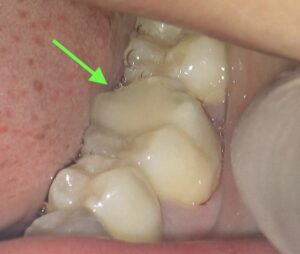

噛んだ時の様子です。

削る前の様子です。

詰め物を削っていくと、奥に本来の歯が見えてきます。

なんと黒くなっており、虫歯がまだ残っています。